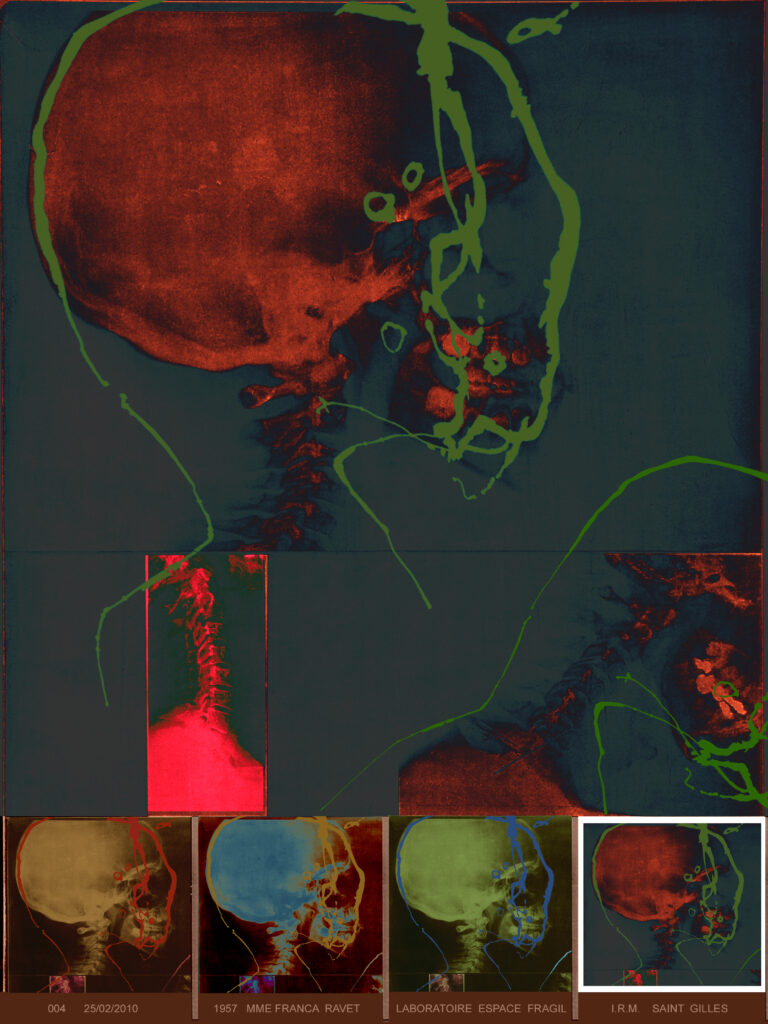

L’artiste est partie d’une empreinte graphique donnée qu’elle assimile à “une sorte d’IRM cérébral”, répétée de manière obsessionnelle et répétitive.

Du point de vue du sens, Ravet restitue ce processus de “conception, de transmission et d’effacement des informations mémorisées tout au long de nos vies”.

En livrant également des grands formats “diasec” sur plexiglas, elle impose un traitement numérique à sa peinture. C’est alors forcément toute la question du fichage et du stockage des données informatiques qui apparaît.